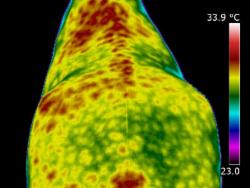

| MUSCLE INJURY | A very valuable use of thermography is in detecting muscle injury. It locates the area of inflammation associated with a muscle or muscle group. It can also show an area of atrophy before it becomes apparent clinically. Atrophy is seen as an area of consistent decrease in circulation when compared to the opposite side. Thermography allows us to see the specific location of strained or torn muscles. It can also help to assess the effects that have been placed on the musculo-skeletal system after extreme exertion and the extent of damage, or secondary damage, after a fall or accident. | | |

| | | When scanning initially, images of the whole horse must be assessed. If a muscle or muscle group shows a raised thermal pattern is the muscle damaged and inflamed or do these muscles simply have increased blood flow because they are working harder to compensate for injury or damage elsewhere? Only a well-trained, experienced thermographer is able to interpret the images.

When inflammation occurs in heavily muscled areas an intense thermal pattern will be evident over the affected area. If oedema and swelling occur over the strained muscle area, the surface temperature may actually become cooler due to subcutaneous fluid accumulation. Both types of images indicate an injury has occurred and careful observations are necessary to detect these differences.